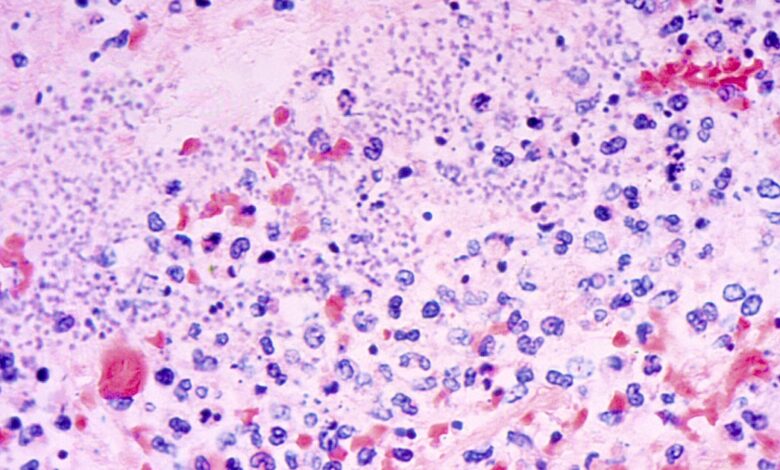

Pneumonic plague is a rare bacterial infection that affects humans, with an average of seven cases reported annually in the United States, mostly concentrated in the western states, according to federal health authorities.

The bubonic plague, transmitted through infected rodents like prairie dogs and rats, is the most common form of this bacterial infection. The other two variants include septicemic plague, affecting the entire body, and pneumonic plague, targeting the lungs.

Pneumonic plague is deemed the most lethal and easily transmissible form of the disease.

The transmission of the bacteria occurs through fleas’ bites, which can pass the infection between rodents, pets, and humans. Additionally, contact with infected bodily fluids can also lead to contracting the plague. Health experts advise caution when handling sick or deceased animals to prevent infection.